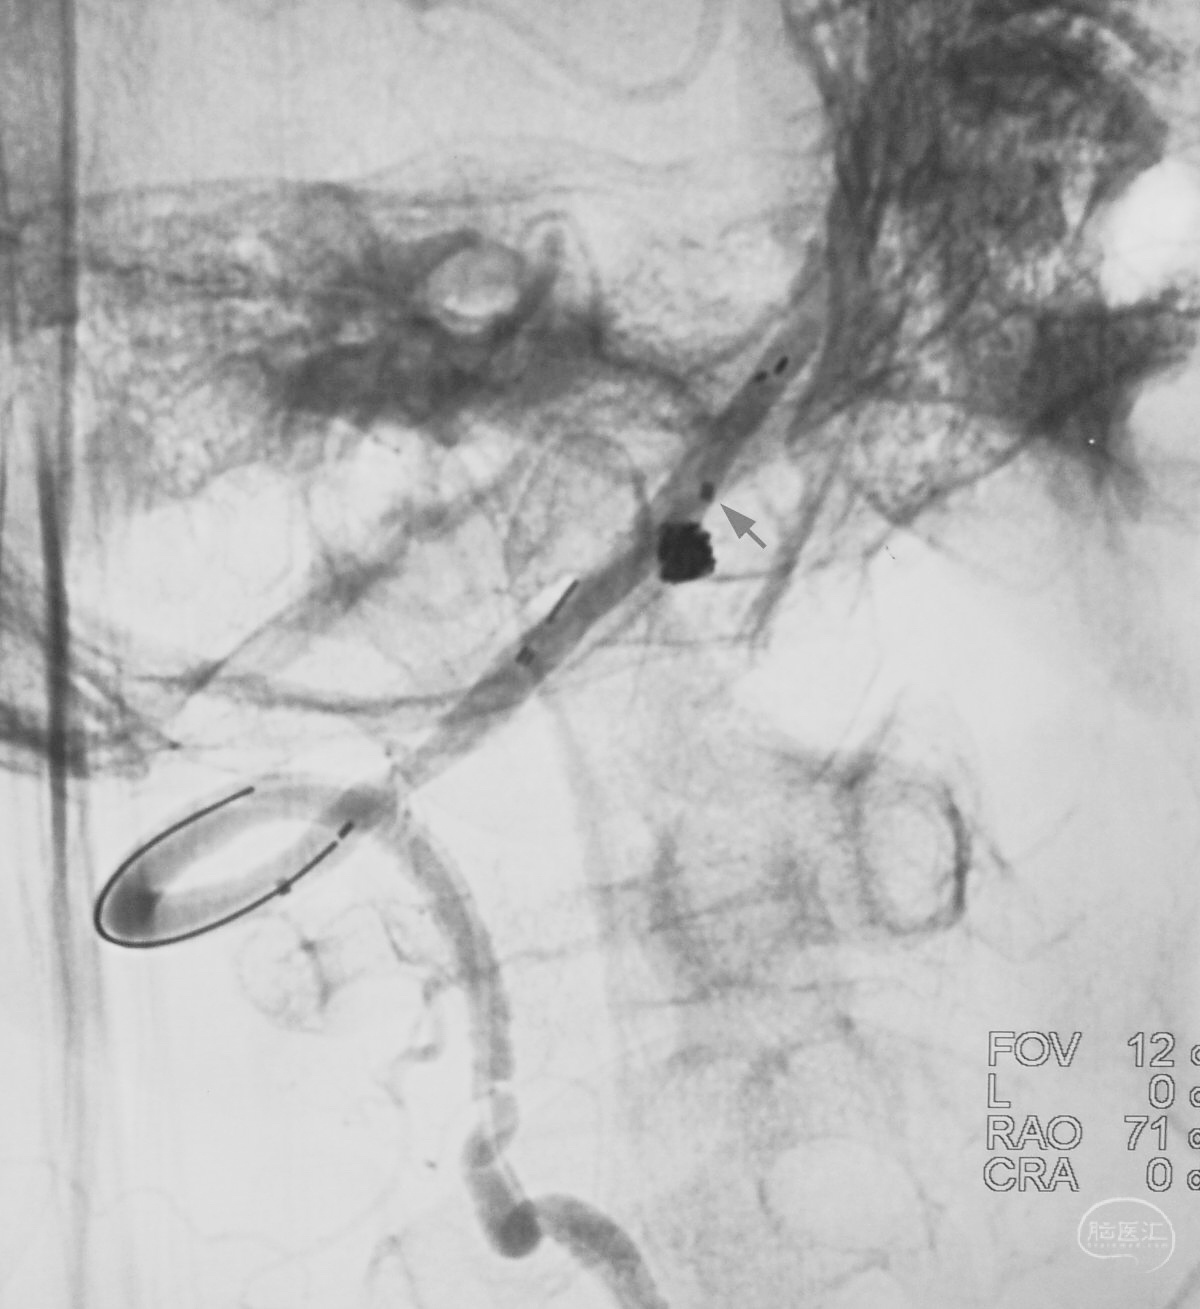

解脱第一枚Solitaire 4×20支架后,套叠置入第二枚Solitaire 4×20支架,置入两枚支架的原因是考虑该瘤是夹层动脉瘤,多支架能够强化血流导向作用,有利于夹层愈合。

术后右椎动脉工作位造影,

以及正位造影显示动脉瘤完全栓塞,载瘤动脉畅通。